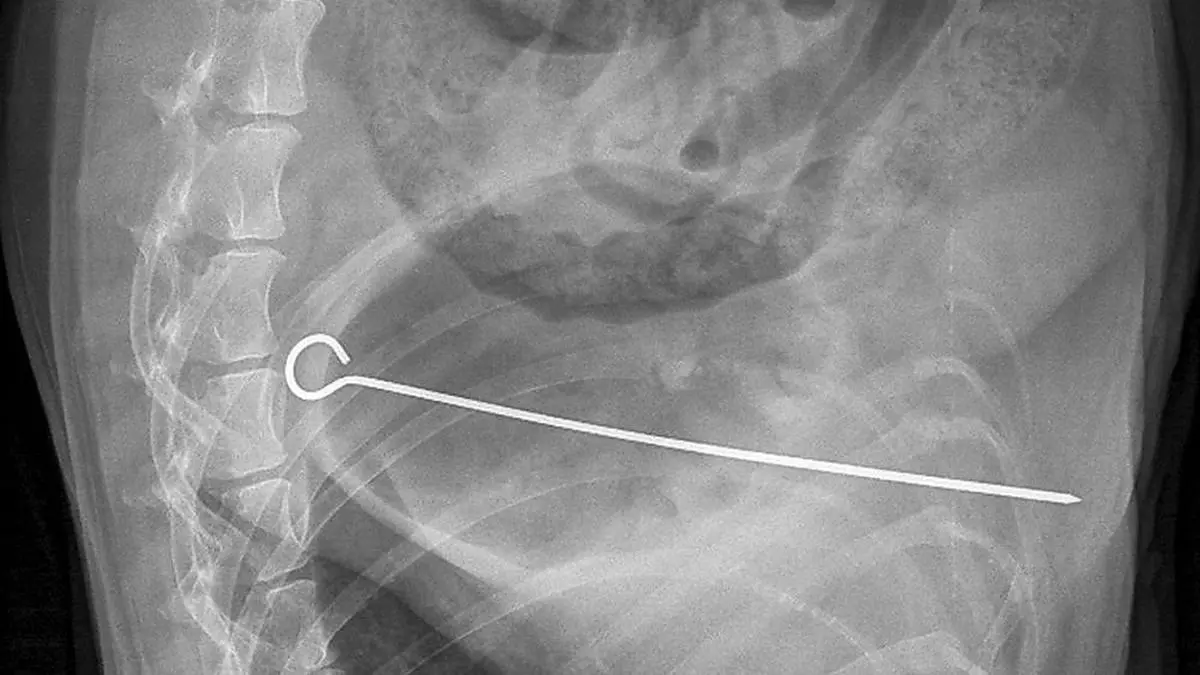

Hund verschluckte zwanzig Zentimeter langen Grillspieß

Ein Hund hat bei einem Grillfest in Schottland einen seltsamen Geschmack bewiesen.